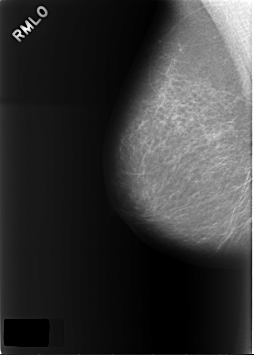

C_0160_1.RIGHT_MLO

RIGHT_MLO LINES 5672 PIXELS_PER_LINE 4064 BITS_PER_PIXEL 12 RESOLUTION 50 NON_OVERLAY